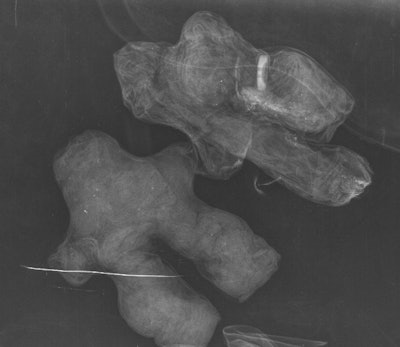

The researchers used a flat-panel digital radiography (DR) system (Clisis, Primax) to examine the objects: Five were individual dolls made of black or red fabric, while one was a pair of dolls bound together with a white cord -- one doll was made of black fabric and the other was made of white fabric. Both a radiologist and a medical anthropologist read the images taken of the dolls on film and on a workstation (JOFRI, December 2015, Vol. 3:4, pp. 221-225).

Two of the dolls made of black fabric included human hair on the head; one of these also included hair on the genital area, which led Charlier's group to characterize it as male. This doll was found to have a button inserted in its right leg, which was bent and shorter than the left leg.

"[The button] could be used to refine the identification of the target subject," Charlier and colleagues wrote.

Two dolls made of black fabric. All images courtesy of Dr. Philippe Charlier, PhD.Two of three red cloth dolls appeared to represent men of different sizes, with hair incorporated at the head and the genitals. One of these dolls had a staple in its filling. The third red doll appeared to have been made with features suggesting a woman's hips; the x-ray showed two separate zippers or fragments of the same side of a zipper.

"The presence of the zipper elements inside of the doll could constitute a love charm which joins and holds two things together," the authors wrote.